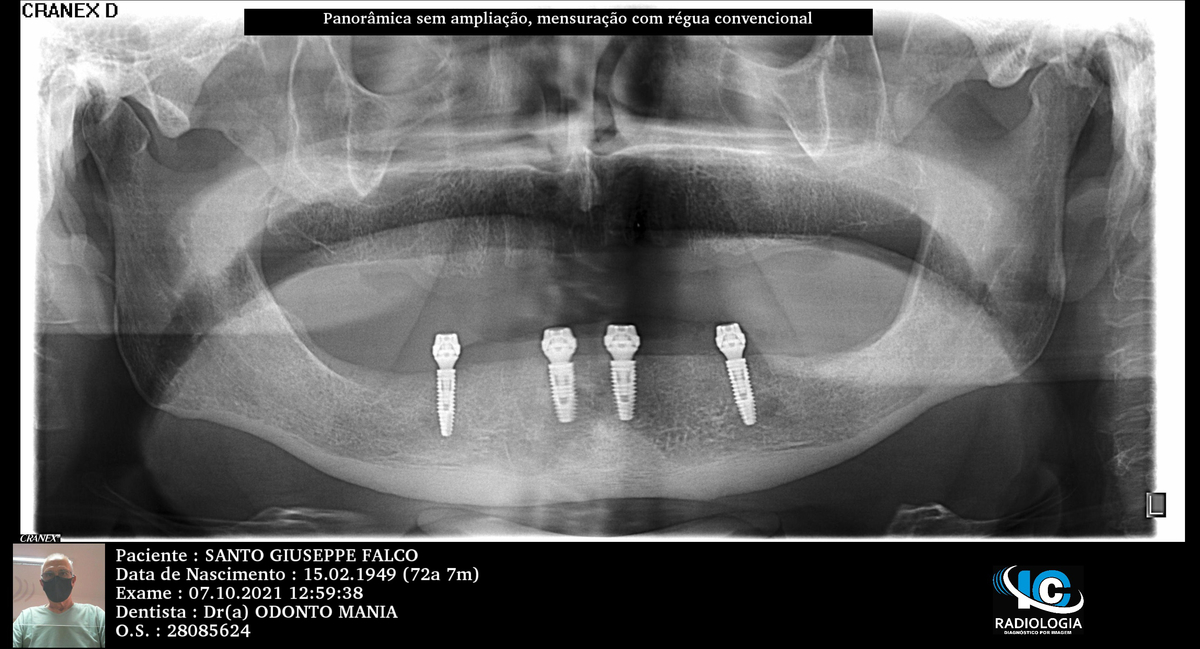

PRÓTESE TOTAL FIXA EM IMPLANTES

S.G.F.